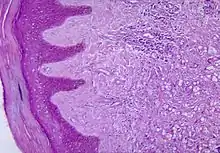

| Histopathological changes in the skin seen in lobomycosis. Source: CDC | |

Diagnosis of Lobo's disease is made by taking a sample of the infected skin (a skin biopsy) and examining it under the microscope. Lacazia loboi is characterized by long chains of spherical cells interconnected by tubules. The cells appear to be yeast-like with a diameter of 5 to 12 μm. Attempts to culture L. loboi have so far been unsuccessful.[10]